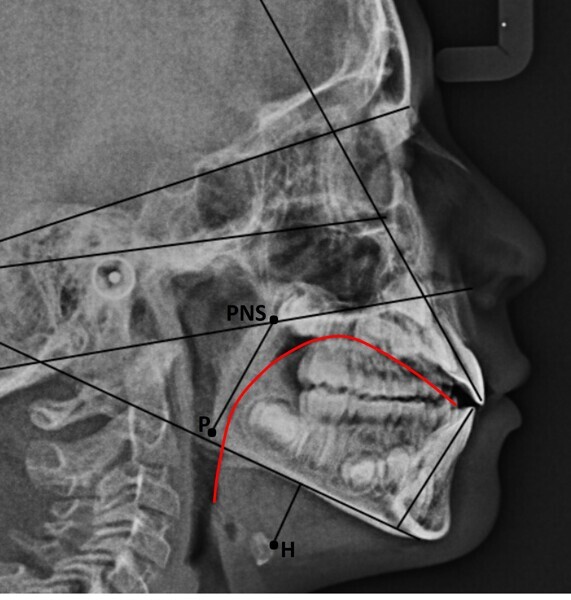

In the control cephalometric radiograph, the lingual position had completely regularised, the body and tip being in contact with the hard palate, creating an average overbite (Fig. 14). The cervical hyper-lordosis was moving towards correction and the skull posture was less forward.

In agreement with Yoon et al.,4 in the radiographs at T0 and T1, we also calculated the length of the soft palate because its increase in size, as far as we know, is considered a risk factor for the development of obstructive sleep apnoea, and its reduction is part of the therapeutic goals of myofunctional therapy for the treatment of obstructive sleep apnoea.28, 29 The P–PNS value had decreased from T0 (30.0 mm) to T1 (29.4 mm). Also in agreement with Yoon et al.,4 we also calculated the length of the perpendicular from the hyoid bone to the mandibular plane. An increase indicates a low tongue posture. This line had fallen from T0 (16.3 mm) to T1 (11.9 mm), giving further confirmation of improved lingual posture.

Comparison of the cephalometric radiographs, with evidence of the new lingual posture (Fig. 16), indicated a balance between the orofacial forces30 that allowed a new growth pattern that was less vertical than the previous one. Long-term follow-up of the patient will tell us whether this pattern will be maintained.